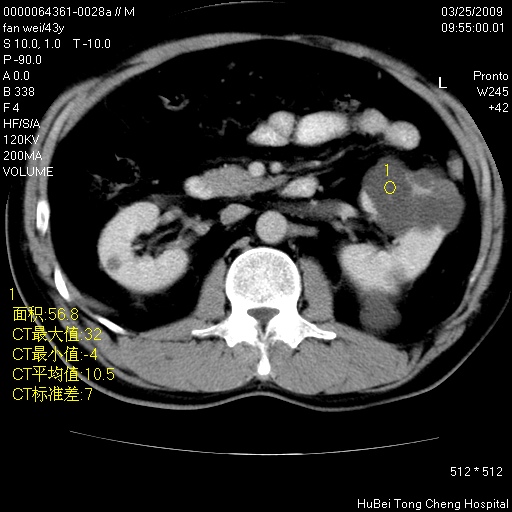

患者 男,43岁。左侧腰部不适两天。平素健康。无家族遗传病史。

腹部彩超提示:1)轻度脂肪肝。2)左肾多发囊性占位性病变;建议行进一步检查。

临床诊断:左肾多发囊性占位性病变,性质待定(多发肾囊肿?)。

双肾ct轴位平扫+增强扫描(层厚10mm,螺距1.0,重建间隔10mm),图像如下: